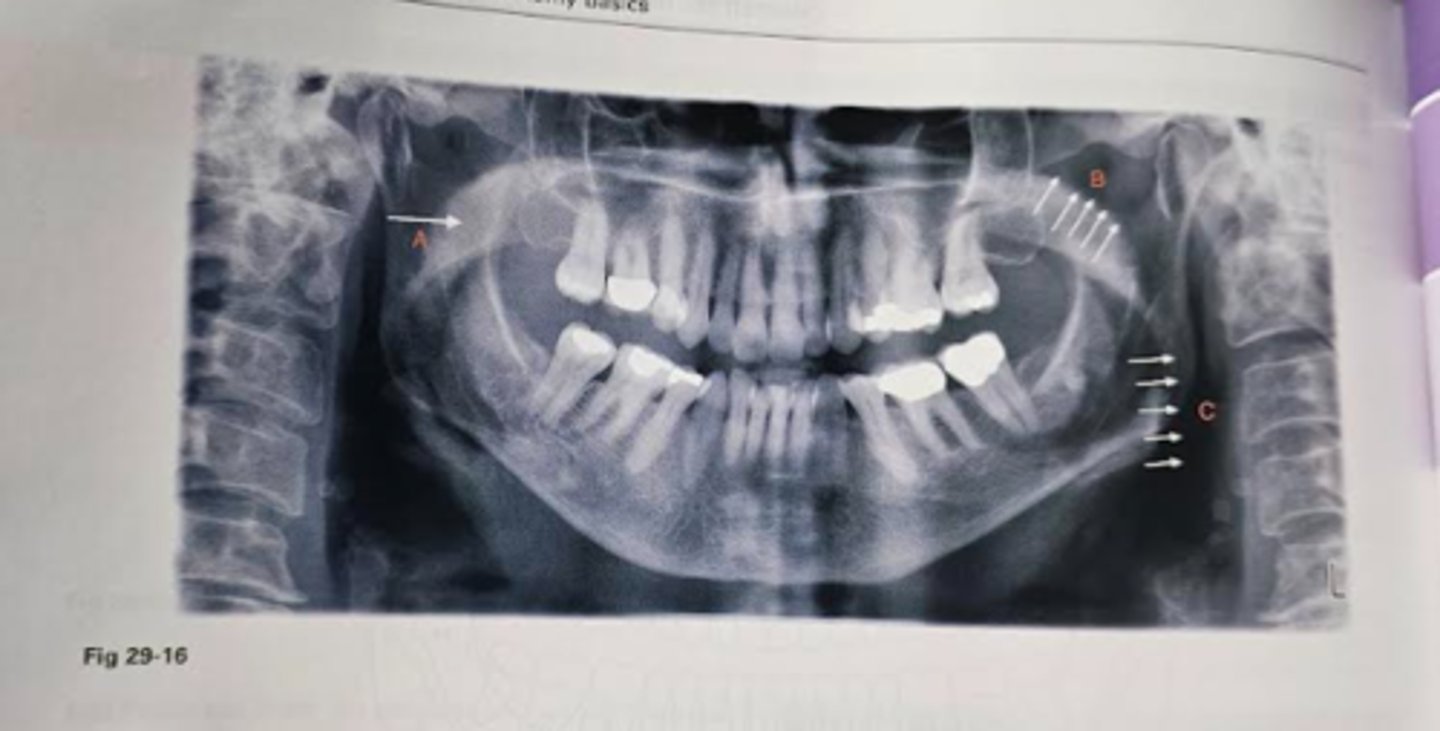

3. In figure 29-16:

Identify the faint radiopacity labeled A

Identify the radiolucent band labeled B

Identify the radiolucent band labeled C

Soft palate

A

Nasopharyngeal air space

B

Glossopharyngeal air space

C